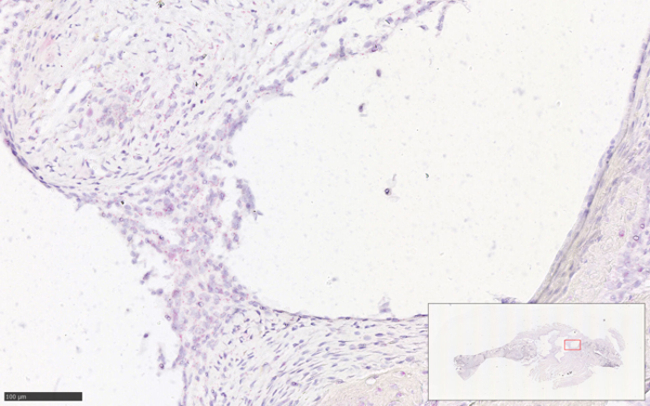

MRONJ-Associated Research

Medication-related osteonecrosis of the jaw (MRONJ) is a potentially severe drug side effect of mainly antiresorptive agents. Key features of this condition include areas of exposed necrotic jawbone, to varying extents. This disease is typically seen in patients suffering from osteoporosis or malignant tumours with bone metastases. Bisphosphonates and the monoclonal antibody Denosumab represent the principle causative drugs. In addition, there are reports that other drugs used for the treatment of cancer (e.g. antiangiogenic agents or tyrosine kinase inhibitors) can also cause MRONJ. With regard to the rapidly increasing incidence of MRONJ in the catchment area of the university hospital, and in respect of the challenges of successful surgical treatment, MRONJ has become one of the major focuses of our research.

In a prospective clinical study, the influence of malnutrition and its treatment will be evaluated in the course of MRONJ. In addition, the quality of life of this highly vulnerable patient collective will be assessed. For the management of complex wounds, vacuum-assisted closure (VAC) therapy has shown beneficial effects for various indications and surgical disciplines. In our department, we have been able to develop a system (patent pending) that allows intraoral application of VAC therapy. As the exact pathophysiology of MRONJ has not yet been fully elucidated, we are currently studying in- cell culture models of how phytotherapeutic agents and other drugs with an inhibitory effect on the NFkB pathway can inhibit the differentiation of osteoclasts, which may contribute to the development of MRONJ. This project is being conducted in cooperation with the laboratory for experimental urology and it is supported by a TWF grant.